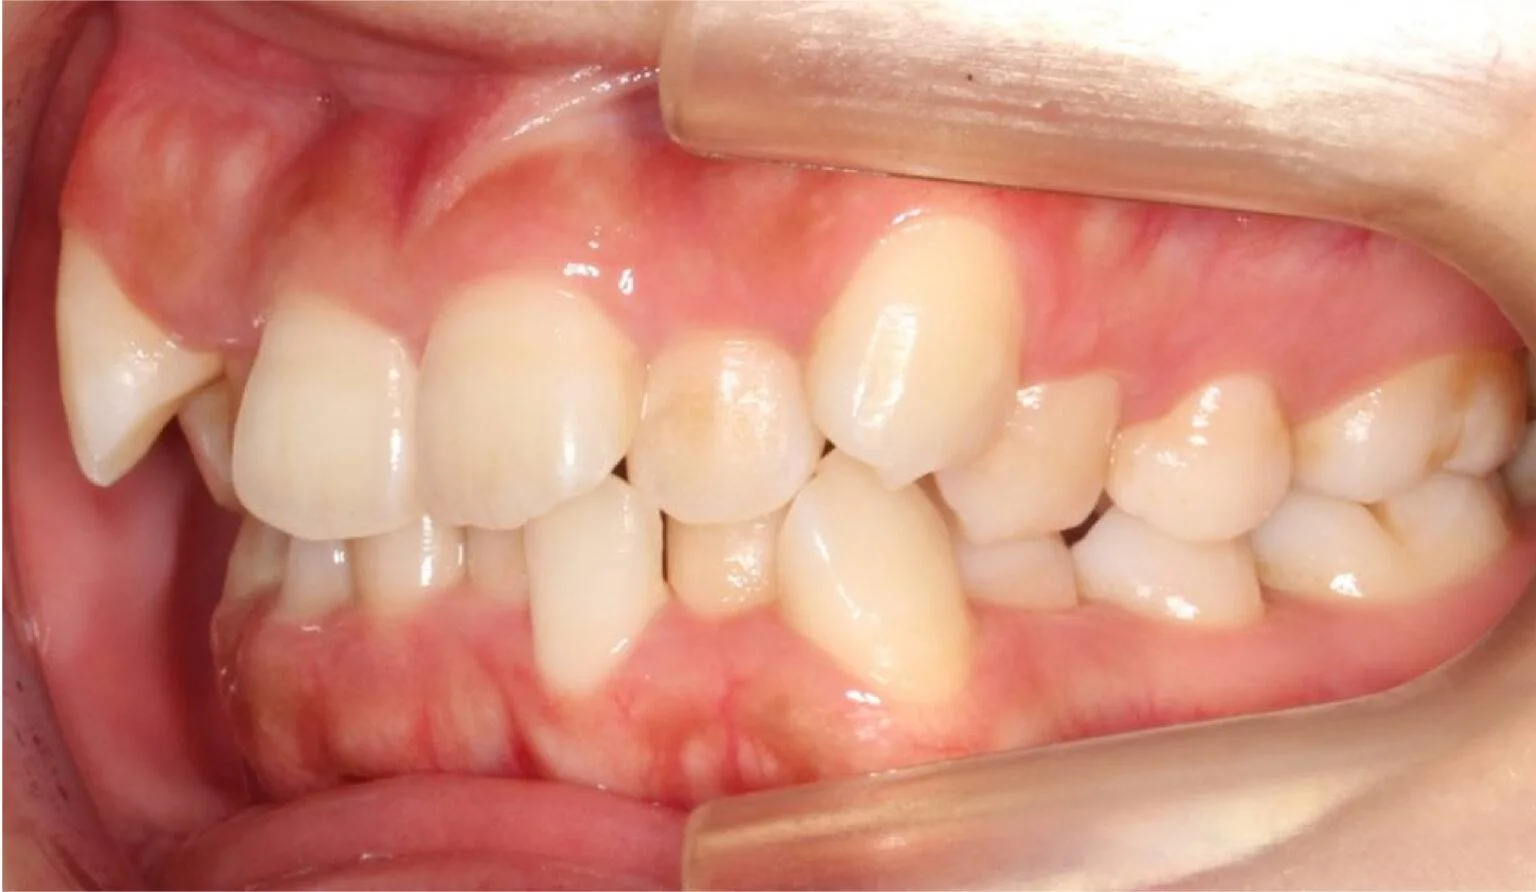

Overcrowding is a common teeth misalignment which occurs due to lack of space in the oral cavity for the teeth. This makes the teeth grow to be crooked and/or overlap with each other. This creates an overcrowded atmosphere in the mouth and can lead to poor oral hygiene due to the inability to clean the teeth efficiently.

This is where the upper teeth horizontally protrude past the bottom teeth, also called an ‘Overbite’. A common dental complaint we hear that relates to protrusion is ‘my front teeth are sticking out’.

The protrusion of teeth can cause speech problems and make it difficult to consume food, this is due to the fact it can prevent correct biting and chewing.

Protrusion is a dental condition that is usually caused by skeletal issues with the lower jaw, mainly in those who have a growth deficiency. Overbites can cause irreparable soft tissue damage and also contribute to early tooth loss from excessive wear of the teeth. Besides overjets having functional side effects, they can also affect the aesthetics of the smile. Overall, it can look unpleasant to the eye, this can affect a person’s psychological and emotional state.

Protruded teeth commonly come in conjunction with patients with narrow arches, habits of tongue thrusting, swallowing and breathing improperly, phonetic problems – such as enunciating certain words and sounds like F and V, and allergies.

This is when the upper teeth bite down on the insides of the lower teeth, this can also be known as a negative overjet. Common dental complaints we hear that relate to a crossbite are “my chin protrudes out”, “my front teeth bite on each other” or “I can’t bite on my back teeth properly”.

A crossbite can happen on either side of the jaw and it affects both the front and back teeth. Crossbites usually occur due to a dental or skeletal problem, or both. These can be caused by habits, bone structure, airway issues, or genetics. Untreated crossbites can affect more than just the teeth, they can cause issues in the jaw. It makes the jaw muscles work at an uneven rate, which causes temporomandibular joint disorder, it can cause headaches and pain in the jaw, neck, or shoulders.